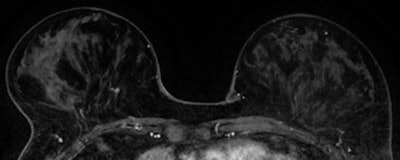

"In the Netherlands, screening changed to digital mammography in 2006, which may have helped earlier detection. Furthermore, women with the BRCA1 and BRCA2 genes at high risk are screened with MRI and mammography. MRI sensitivity increased in and after 2006, during which time the results of MRI and mammography also improved," she noted.